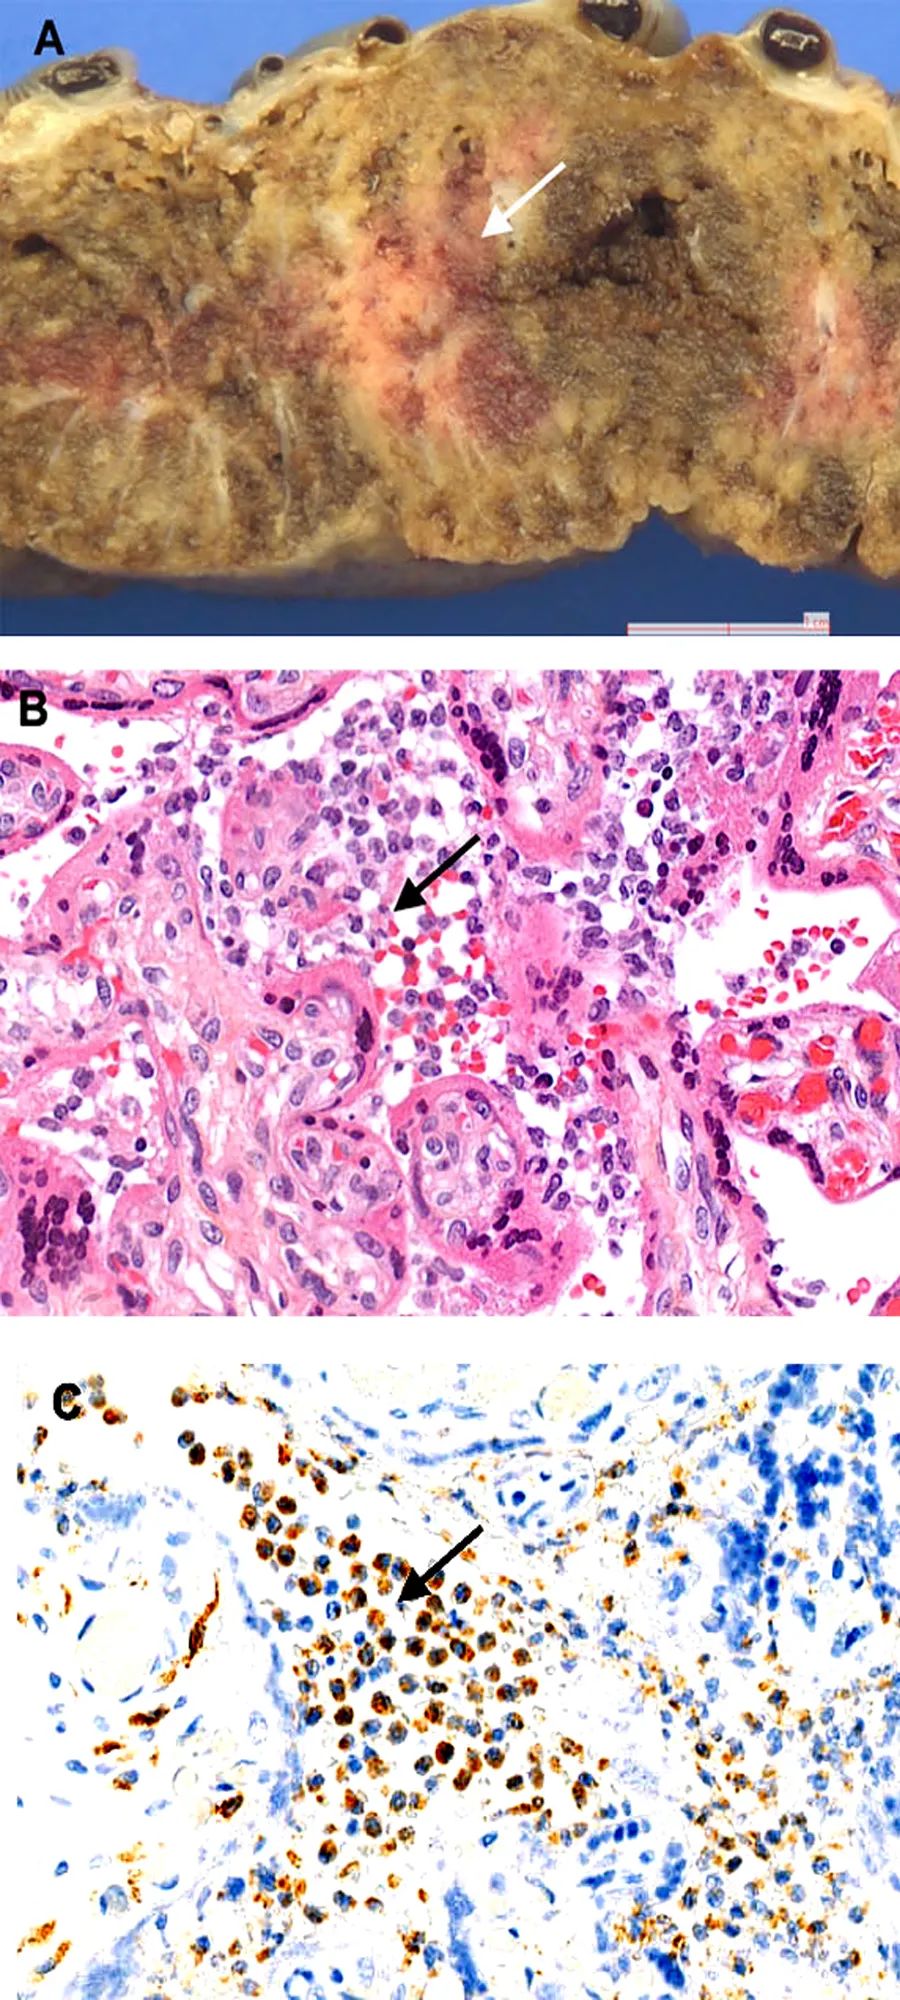

胎盘组织病理学检查显示弥漫性绒毛周围纤维蛋白沉积,伴有梗死和急性和慢性绒毛间质增生。下图显示了胎盘大体和显微镜检查以及免疫组织化学的结果。

用抗SARS-CoV-2n蛋白抗体进行免疫染色,可见绒毛周围滋养层细胞胞浆呈强阳性。特殊染色及免疫组化均未发现其他致病菌。